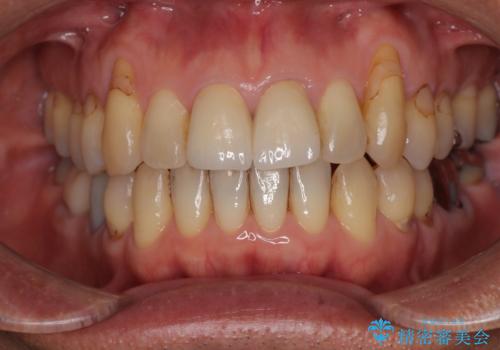

左右対称の2本の歯にセラミッククラウンを装着したことで、調和の取れた審美的な口元となりました。